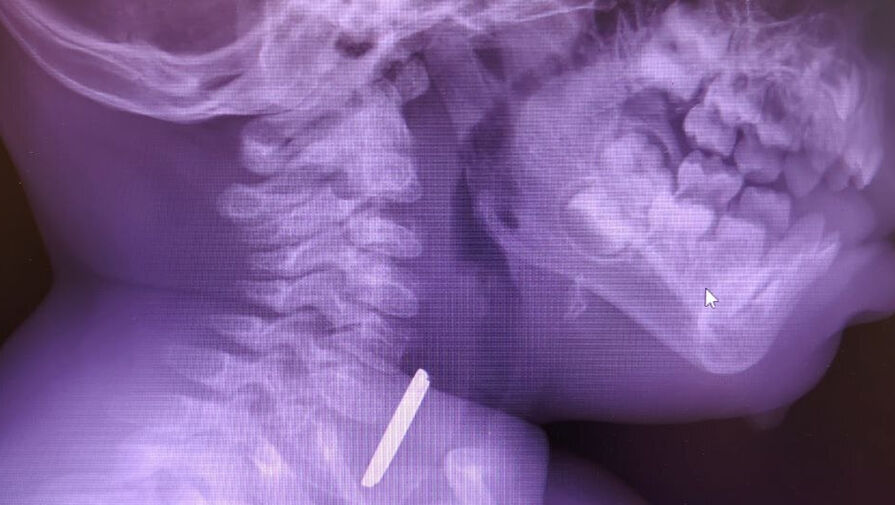

Маленький пациент поступил в больницу с затрудненным глотанием и слюноотделением. Ребенка направили на рентген, который показал наличие батарейки в верхней трети пищевода. Пациента направили направили на экстренную операцию, и под наркозом извлекли предмет, который уже успел причинить здоровью младенца вред.

«Батарейка повредила стенку пищевода, вызвав глубокий электрохимический ожог, занимающий половину просвета пищевода. Учитывая тяжесть состояния от полученной травмы, ребенок был госпитализирован в отделение реанимации, где проводилась интенсивная терапия», — рассказал детский хирург детской больницы Вячеслав Воронин.